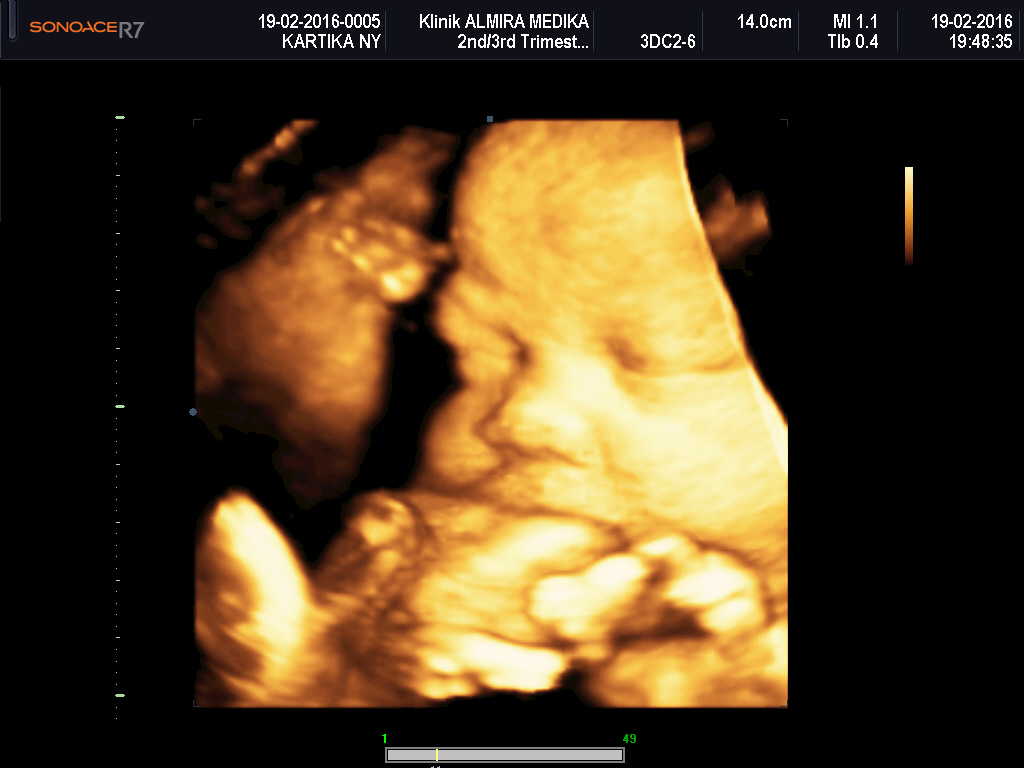

ALMIRA MEDIKA USG KANDUNGAN 4 DIMENSI SURABAYA SIDOARJO MURAH

Apa itu USG USG atau Ultrasonografi merupakan suatu alat penunjang diagnostik di bidang kedokteran sebagai sarana pencitraan untuk mendiagnosa suatu penyakit. USG mentrasnfer energi dari daya output mesin ke lapisan-lapisan tubuh yang diperiksa. Alat ini dapat mendeteksi organ dalam, otot, struktur organ dan tulang, serta adanya gangguan patologis. Arti dari warna pada hasil USG yaitu: Warna hitam mengartikan cairan Warna abu-abu berarti jaringan Warna putih mengartikan tulang Hasil USG warna abu-abu yang biasanya mendominasi area sekitar gambar USG menunjukkan area jaringan rahim Anda. Kemudian warna hitam yang Anda lihat di dalamnya merupakan cairan ketuban yang mengelilingi bayi.